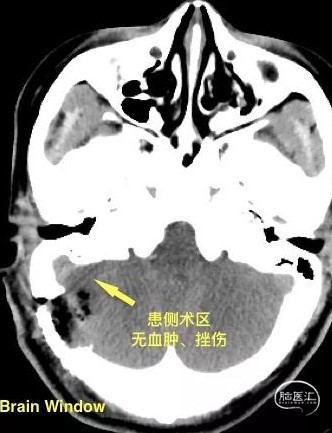

3. 术后影像,头颅CT(术后次日2021-09-27)。